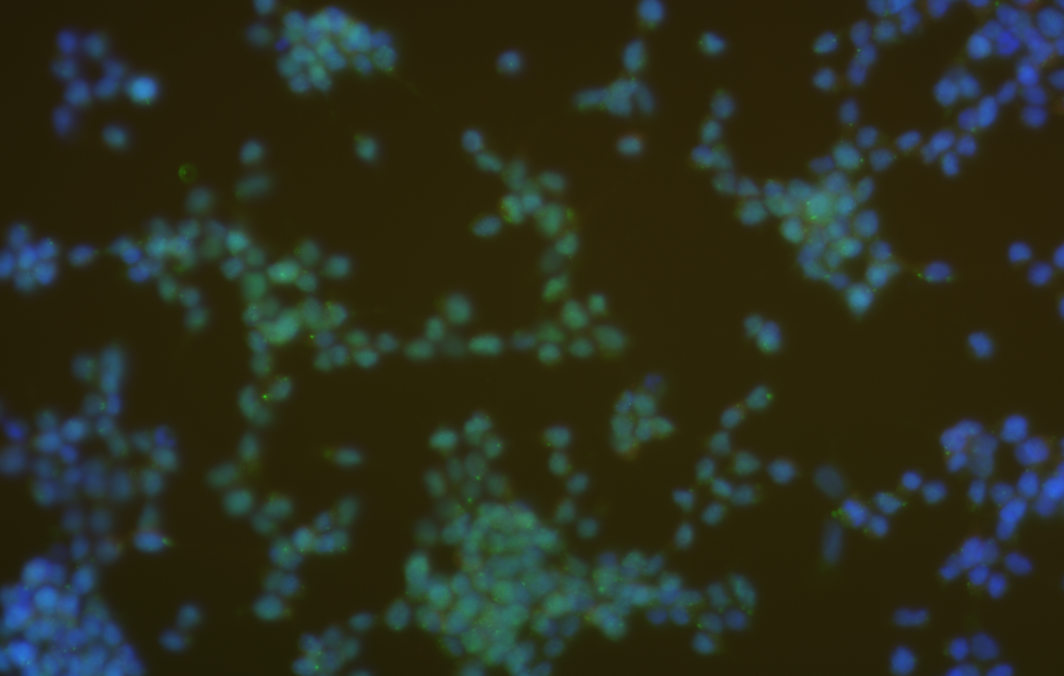

免疫熒光(Immunofluorescence),也稱為熒光抗體技術(shù),是一種利用熒光素標(biāo)記的抗體與抗原特異性結(jié)合的原理,對(duì)細(xì)胞或組織的特定抗原進(jìn)行檢測(cè)的技術(shù)。該技術(shù)主要應(yīng)用于生物學(xué)、醫(yī)學(xué)及臨床診斷等領(lǐng)域,目的是對(duì)細(xì)胞或組織的特定成分進(jìn)行快速、靈敏的檢測(cè)。

免疫熒光的主要步驟包括:樣本處理、抗體標(biāo)記及熒光檢測(cè)。其中,樣本處理與免疫組化相似,需要將組織或細(xì)胞固定、切片等,以便抗體能夠與抗原進(jìn)行有效的結(jié)合。抗體標(biāo)記是將抗體與熒光素結(jié)合,以便在熒光檢測(cè)環(huán)節(jié)實(shí)現(xiàn)對(duì)特定抗原的檢測(cè)。熒光檢測(cè)則是通過(guò)熒光顯微鏡觀察熒光信號(hào),實(shí)現(xiàn)對(duì)特定抗原的定位和定性分析

免疫熒光